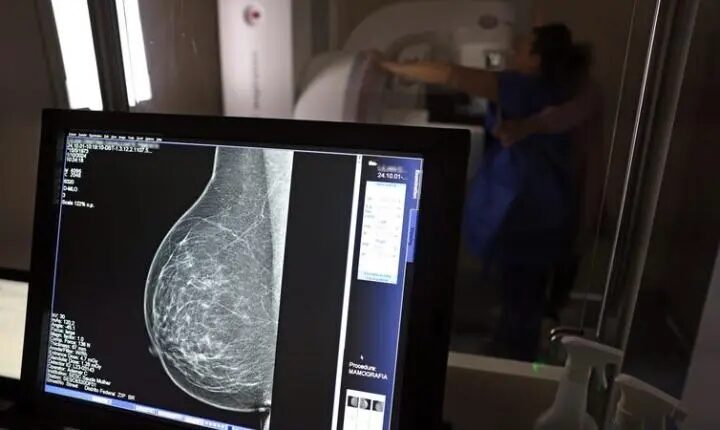

Atlas da Radiologia mostra que país tem baixa cobertura de mamografias, 24%. O ideal, recomendado pela OMS, é de 70%.

A OMS é citada como a referência para a cobertura ideal de mamografias, servindo como um parâmetro para a análise da situação brasileira.